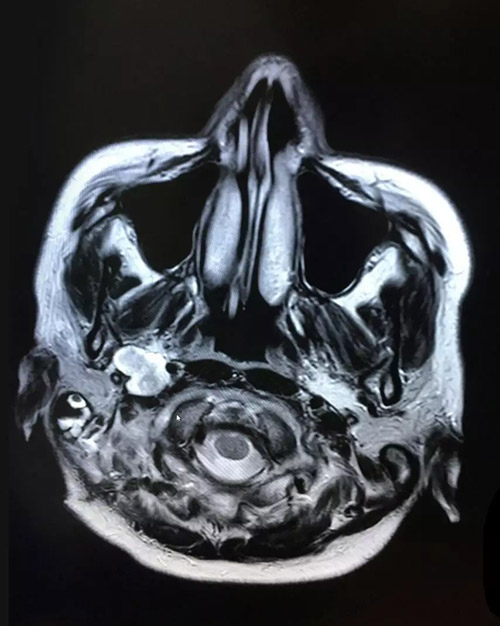

术后影像:右侧桥小脑角区,颈深部占位术后改变